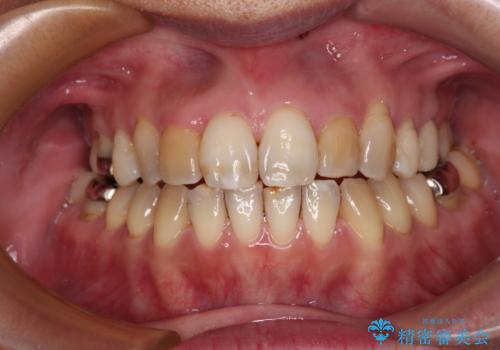

前歯の後戻り インビザラインでの再矯正治療

- かつて抜歯矯正を行ったものの、後戻りをしてしまったとのことで来院された患者様です。

上顎前歯が前突し、隣の歯が裏側に移動してきている状態でした。

飲み込みの状態を確認したところ、舌の突出癖が認められたため、それによる後戻りの可能性が高いと考え、舌のトレーニングを指導しました。

舌のトレーニングをしっかりと行ってくださり、10ヶ月で希望通りの歯列となりました。

日頃から飲まれる飲み物の影響で着色しやすいため、来院の度に着色除去のクリーニングも行っていました。